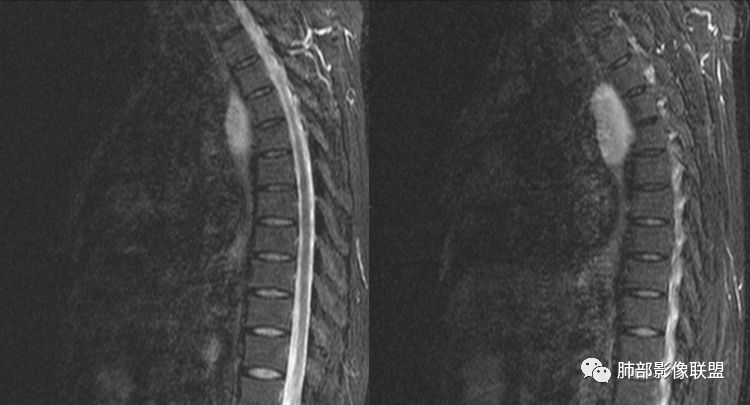

男性,43岁,体检发现后纵隔占位,边缘光整,CT示密度均匀,周围组织受压移位,无钙化囊变及脂肪组织,增强未见明显强化。MRI:T1示肿块信号较肌肉高,T2不均匀高信号。考虑为良性病变,第一是神经节细胞瘤,其次是支气管源性囊肿。

中年男性,无症状,后纵隔肿块,长径大矢状位于横径,质地偏软,塑形,等t1稍长t2,比较均质,增强轻微强化,与脊柱,主动脉,食管脂肪间隙存在,部分层面与脊柱相贴,骨质无改变,周围无肿大淋巴结,考虑神经源性肿瘤,节细胞神经瘤可能大,鉴别心包斜窦,淋巴瘤,淋巴管囊肿。

后纵隔占位,椭圆形,边缘不规则,CT低密度,MRI长稍长T1稍长T2信号,增强扫描未见强化,支气管受压。囊性病变,考虑支气管囊肿(常见,T1WI稍低“比水高”T2WI稍高,可能与其内含有粘液或蛋白有关);鉴别淋巴管囊肿(更软塑性性更大,接近纯水MRI信号长T1长T2,受周围挤压更明显,变形。);神经节细胞瘤瘤(增强可有轻度渐进性强化,也可不强化,关键是不常见),还有就是神经源性囊肿与肠源性性囊肿。

后纵隔囊性占位,密度均匀,与左主支气管分界不清,略受压,增强后强化不明显,核磁上看肿块局部突出,信号欠均匀,考虑良性,节细胞神经瘤可能大,支气管囊肿待排。

左后纵隔食管旁占位,边界清晰,增强目测未见明显强化,稍长T1稍长T2信号,信号尚均匀,病灶较软,和食管紧贴,定性良性,首先考虑前肠囊肿,以支气管囊肿可能性大,鉴别节细胞瘤。